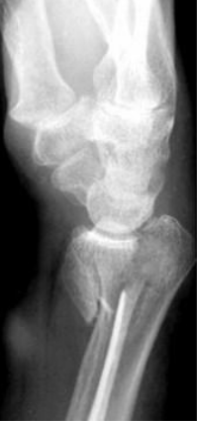

En un paciente con una fractura con esta radiografia, que tratamiento se recomienda?

Clavillos + yeso, fijador externo o placas

Fractura que se presenta en esta radiografia

Fractura de Smith

Mecanismo de accion de esta fractura

Caida sobre mano en flexion con antebrazo en supinacion

Deformida que presentan los pacientes con esta fractura

En pala de jardin